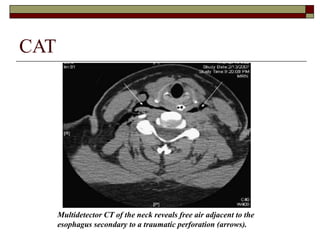

 CAT :

 En trauma penetrante: diagnóstico de lesiones

del confluyente laringotraqueal, como

complemento de la laringoscopía y

broncoscopía

 En trauma cerrado: evaluación de la laringe,

fracturas o lesiones complejas de la columna

vertebral o médula espinal

CAT

Multidetector CT of the neck reveals free air adjacent to the

esophagus secondary to a traumatic perforation (arrows).